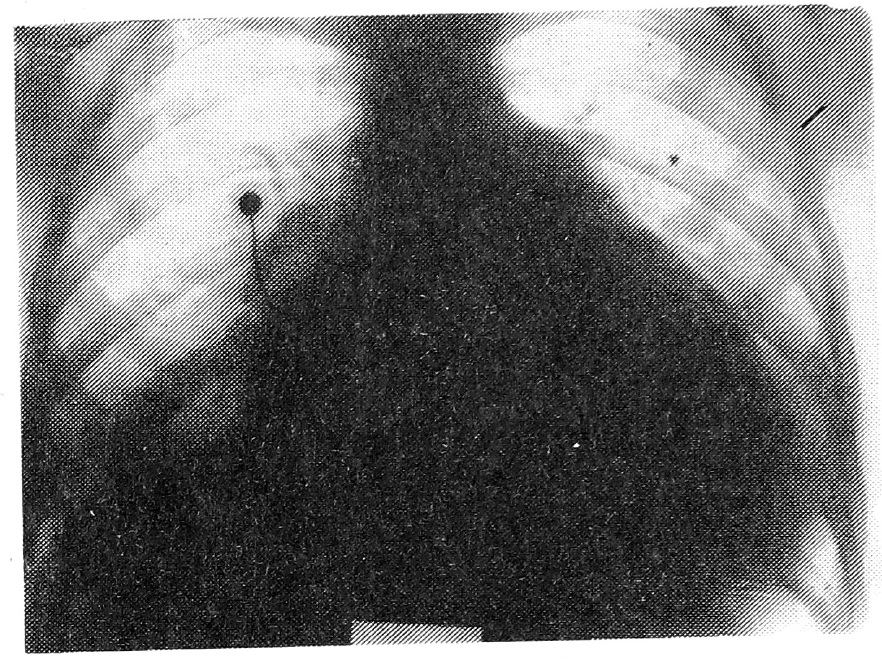

Рентгенограмма: сосудистый рисунок усилен за счет венозного застоя. Легочная артерия и левое предсердие расширены, поперечник сердца увеличен в обе стороны, кардио-торакальный индекс — 65%; определяется очень слабая пульсация дуг левого контура (рис. 2).

После интенсивного лечения сердечными гликозидами, мочегонными, нитратами состояние больной улучшилось: уменьшилась одышка, сократилась печень, отмечалась положительная ЭХО-кардиографическая динамика. Была выписана 31.08.1989 г. Амбулаторно продолжала принимать сердечные гликозиды и мочегонные. В ноябре после физических и психических перегрузок почувствовала себя хуже: усилилась одышка, появились отеки на ногах. В связи с нарастанием сердечной недостаточности 14.11.1989 г. вновь была госпитализирована в областной кардиодиспансер. Рентгенологически имели место усиление признаков застоя в легких, выпот в правой плевральной полости (рис. 3).

Рис. 3. Рентгенограмма. Описание в тексте.